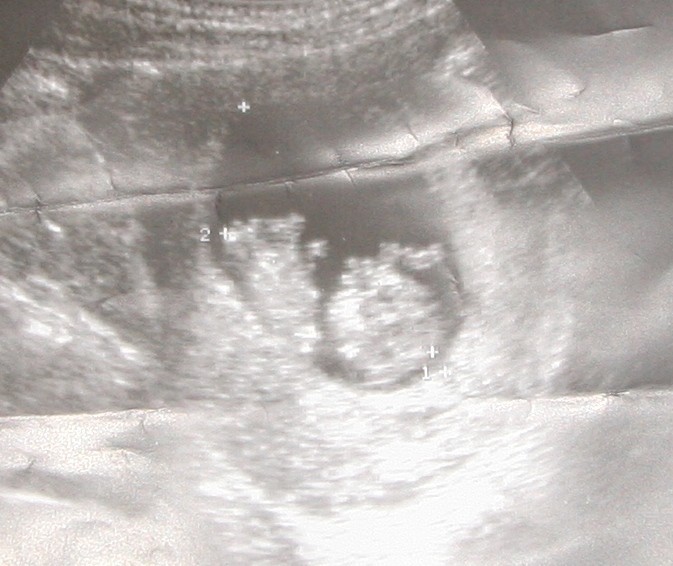

2.a to rezultat w 10t4dc.......sorki za jakość zdjeć ale Wika mi pogniotla i ciezko było zrobic fotkę...ktosik 4cm22mm

• ktosik 10t4dc.jpg

ktosik 10t4dc.jpg

100,7 KB · Wyświetleń: 55